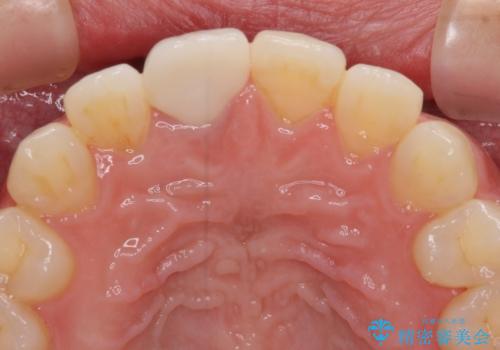

不自然なセラミッククラウンを自然なセラミックに

- 近医にて被せた前歯のクラウンの色の違いを気にして来院された患者様です。

オーダーメイドのオールセラミッククラウンにて補綴することとしました。

元々すきっ歯であったため、隙間を全て埋めると左右で大きさがアンバランスとなることが懸念されました。

違和感のない程度に隙間を小さくして、自然な見た目に仕上げました。